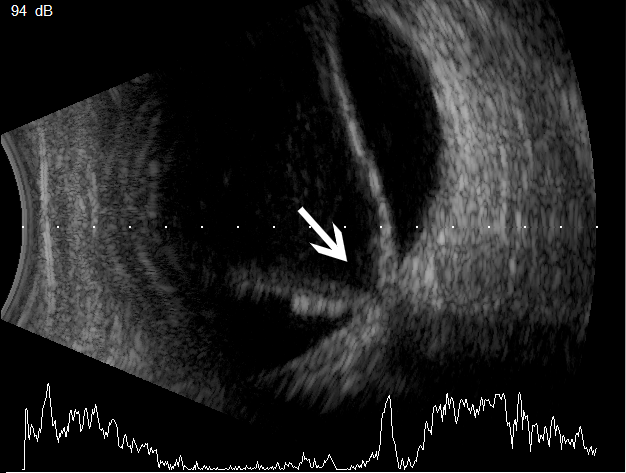

视网膜脱离

此病俗称“网脱”,较为严重,不及时诊治,有失明可能。表现为视物有云雾状阴影,视物变形,视野变小,视物遮挡,黄斑区视网膜脱离时,中心视力急剧下降。

眼科ab超检查单怎么看常见眼底疾病检查结果的秒懂解读_https://www.jmylbn.com_新闻资讯_第27张

B超:脱离的视网膜与视神经相连,呈“漏斗状V字形”

图片来源:天津市眼科医院